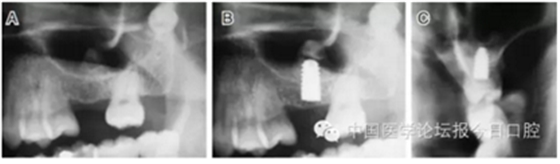

病例3 有骨間隔(圖5)

圖5